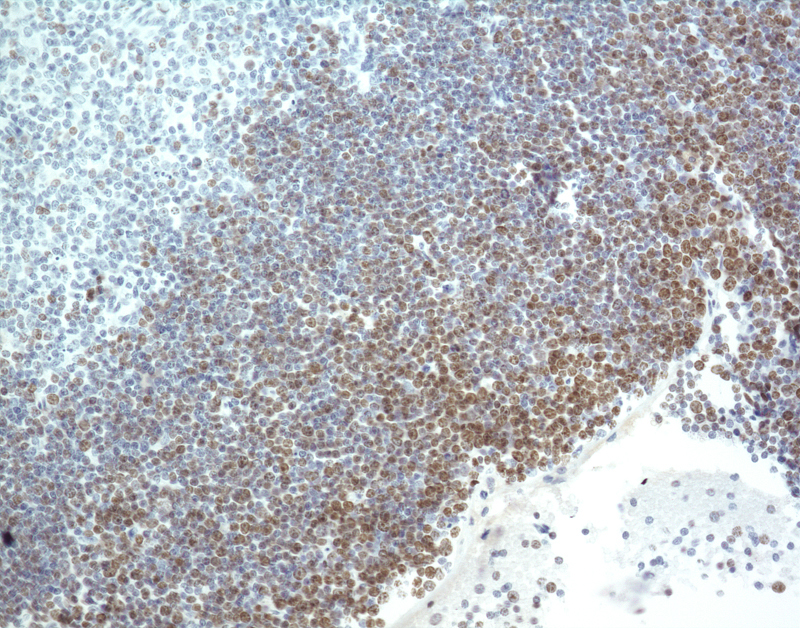

Thymus - Normal tissue. There is moderate to strong diffuse nuclear labeling for Mki67 of thymocytes in the cortex of the thymus.

Thymus - Normal tissue.

IHC for Ki-67